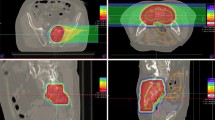

Local tumor recurrence was observed in one patient 6 months after carbon ion radiotherapy (Fig. 4a–c). This patient died 4.5 months later. The estimated 1‑year LC rate was 87.5% (Fig. 3b). Another two patients presented with regional tumor recurrences outside of the high-dose radiation area. These regional tumor recurrences occurred 7 months and 3.5 years after carbon ion radiotherapy. The corresponding estimated 1‑year locoregional control was 75%. One representative regional tumor recurrence is shown in Fig. 4d–f and 4g–i.

a–c Baseline imaging (a), radiation plan (b), and follow-up imaging (c) of a locally recurrent pancreatic cancer (LRPC) patient showing local tumor recurrence (white arrows) after carbon ion radiotherapy. d–f Baseline imaging (d), radiation plan (e), and follow-up imaging (f) of another LRPC patient showing stable local disease (white arrows) after radiotherapy. g–i Corresponding images of the same patient as in d–f at a more distal location, showing regional tumor recurrence (white arrow) in follow-up imaging (i). The tumor recurrence occurred in the low-dose area (10% isodose line) of the performed radiation (h) and was therefore defined as regional tumor recurrence